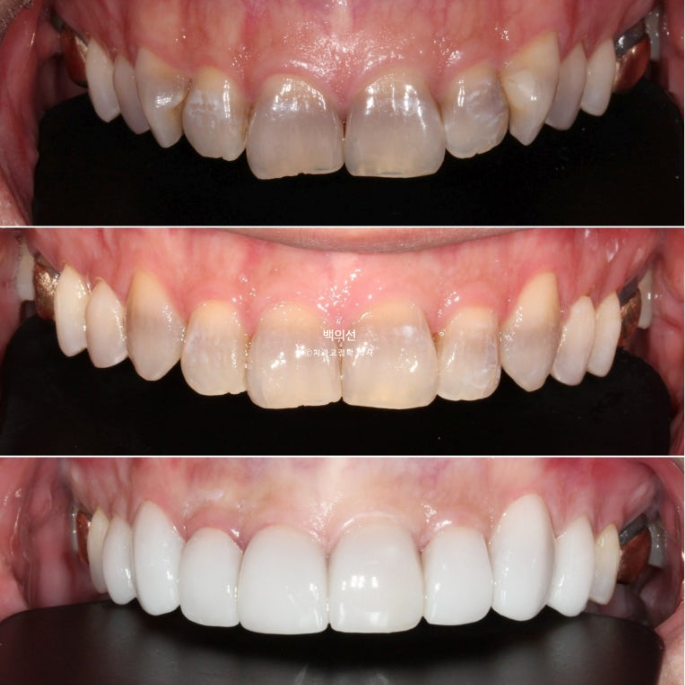

Now let’s compare the initial visit, after orthodontic treatment, and after Gelami in sequence.

No-prep laminate has to be made thin, so the original tooth color inevitably shows through to some extent. In the facial photo, it can be seen that the original dark gray tooth color is showing through.

The way to prevent this gray tone from showing through is to remove some tooth structure and make the laminate thicker.

However, the patient wanted a no-prep approach, so we decided to accept some degree of gray tone.